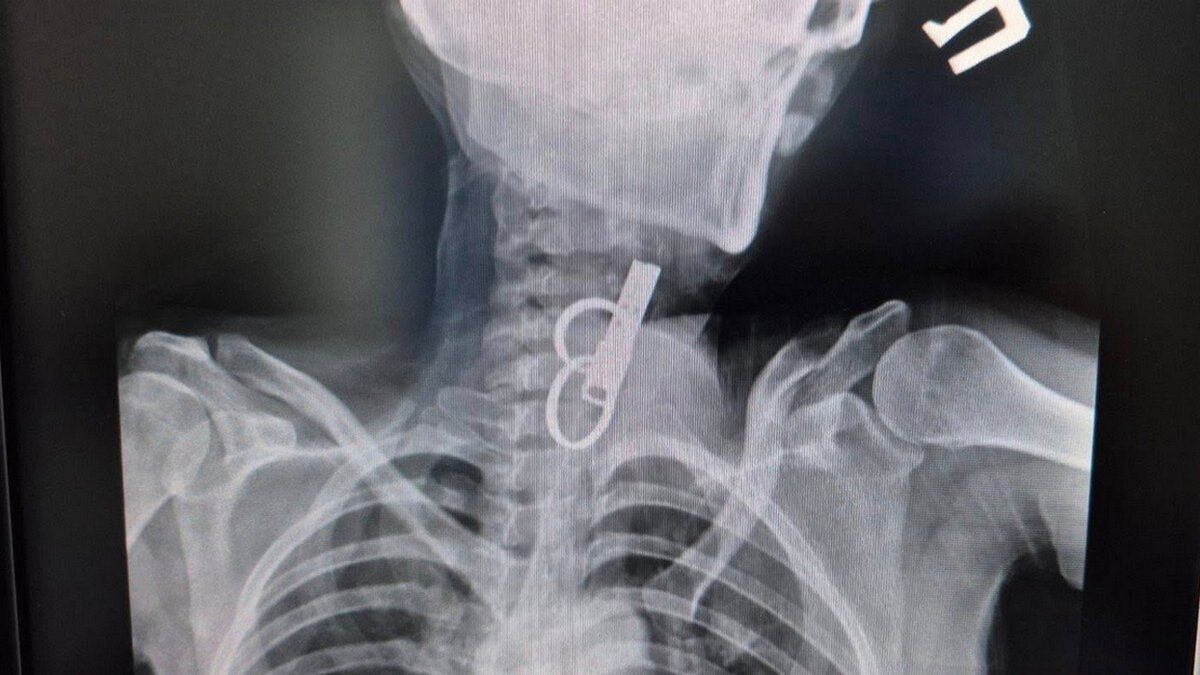

Сторонній предмет на знімку. Фото: Facebook Гусятинської комунальної лікарні

Операційна команда складалася з хірурга О.М. Садового, асистента О.Й. Малковича та лікаря-анестезіолога М.С. Чулика. Їхня швидка реакція та злагоджена робота дозволили успішно завершити складне втручання.

Після втручання пацієнтка перебувала у відділенні анестезіології та інтенсивної терапії. Згодом її перевели до загальнохірургічного відділення для подальшого лікування та спостереження. Загрози для життя немає.